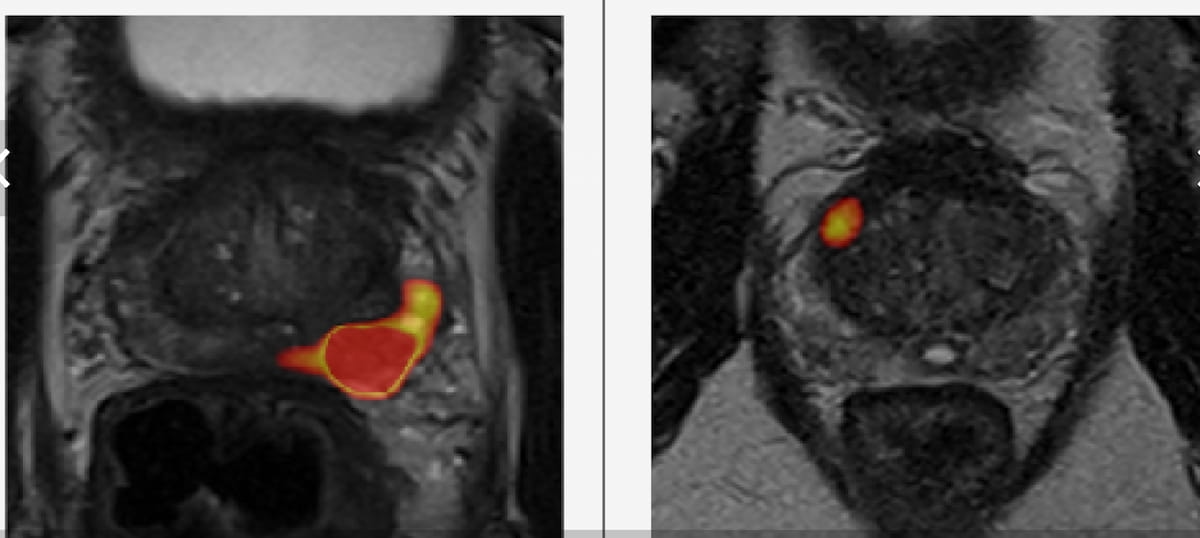

Catch up on the most well-read magnetic resonance imaging (MRI) articles from 2023.

Through assessment of diffusion tensor MRI of the brain, a new AI system reportedly offers a 97 percent sensitivity rate in diagnosing autism in children between two to four years of age, according to research to be presented at the annual Radiological Society of North America (RSNA) conference next week.